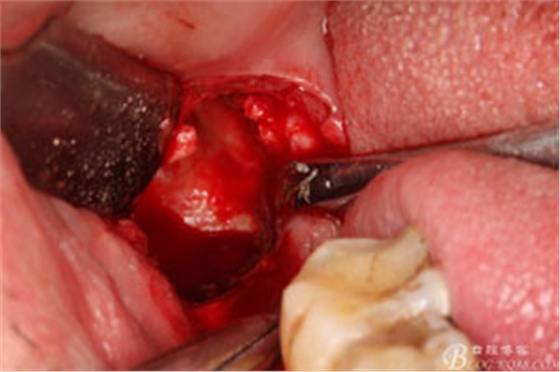

圖7.高速牙鉆去骨。逐漸可見48的牙冠

圖8.刮除牙冠表面的肉芽組織后,可見48 的牙冠